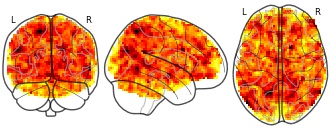

Effects of bariatric surgery on resting state functional connectivity of the...

- neurovault.org

niftiUpdated Mar 22, 2021+ more versions Share

Share Facebook

Facebook Twitter

Twitter EmailClick to copy linkLink copied

EmailClick to copy linkLink copied Cite(2021). Effects of bariatric surgery on resting state functional connectivity of the NAcc (reward network) and PCC (default mode network): Main effect of group on PCC (DMN) connectivity [Dataset]. http://identifiers.org/neurovault.image:445810niftiAvailable download formatsUnique identifierhttps://identifiers.org/neurovault.image:445810Dataset updatedMar 22, 2021License

Cite(2021). Effects of bariatric surgery on resting state functional connectivity of the NAcc (reward network) and PCC (default mode network): Main effect of group on PCC (DMN) connectivity [Dataset]. http://identifiers.org/neurovault.image:445810niftiAvailable download formatsUnique identifierhttps://identifiers.org/neurovault.image:445810Dataset updatedMar 22, 2021LicenseCC0 1.0 Universal Public Domain Dedicationhttps://creativecommons.org/publicdomain/zero/1.0/

License information was derived automaticallyDescriptionModel CA1, BARS larger than NBARS

Contrast: 1 | 1 | -1 | -1Collection description

Obesity imposes serious health risks and involves alterations in resting-state functional connectivity of brain networks involved in eating behavior. Bariatric surgery is an effective treatment, but its effects on functional connectivity are still under debate. In this pre-registered study, we investigated the effects of bariatric surgery on major resting-state brain networks (reward and default mode network) in a longitudinal controlled design.

33 bariatric surgery patients and 15 obese waiting-list control patients (37 females; aged 44.15 ± 11.86 SD years (range 21-68)) underwent magnetic resonance imaging at baseline, after 6 and 12 months. We conducted a pre-registered whole-brain time-by-group interaction analysis, and a time-by-group interaction analysis on within-network connectivity (https://osf.io/f8tpn/, https://osf.io/59bh7/). In exploratory analyses, we investigated the effects of weight loss and head motion.

Bariatric surgery compared to waiting did not significantly affect functional connectivity (FWE-corrected p > .05), neither whole-brain nor within-network. In exploratory analyses, surgery-related BMI decrease (FWE-corrected p = .041) and higher average head motion (FWE-corrected p = .021) resulted in significantly stronger connectivity of the reward network with medial posterior frontal regions.

This pre-registered well-controlled study did not support a strong effect of bariatric surgery, compared to waiting, on major resting-state brain networks after 6 months. Exploratory analyses indicated that head motion might have confounded the effects. Data pooling and more rigorous control of within-scanner head motion during data acquisition are needed to substantiate effects of bariatric surgery on brain organization.Subject species

homo sapiens

Modality

fMRI-BOLD

Analysis level

group

Cognitive paradigm (task)

rest eyes closed

Map type

Z